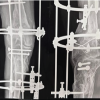

A 68-year-old lady presented in the outpatient department with a complaint of pain in the left thigh and inability to bear weight for the past 12 years. The patient initially suffered a road traffic accident leading to an isolated subtrochanter femur fracture on the left side (Fig. 1). The patient was initially managed with a femur nail (Fig. 2) but always complained of pain and inability to bear weight on that limb since then. The patient was re-operated, probably for non-union at the fracture site after 3 years of the index surgery. The patient was managed with a proximal femur locking plate with autologous bone grafting. The patient was partial weight bearing on that limb for the next 3 years. The patient was never pain-free nor able to bear full weight on that limb. The pain subsequently increased over the period of the next 3 years. The radiographs depicted a broken femur locking plate with no union at the fracture site (Fig. 3). The patient again underwent revision surgery with proximal femur nail and autologous bone grafting. The patient was also given an injection of teriparatide for 3 months. The next 3 years were uneventful with bearable pain and partial weight-bearing mobilization with a walker. The patient one day suffered a jerky movement leading to exaggerated pain in the left thigh. The radiographs depicted a broken proximal femur nail and non-union at the fracture site (Fig. 4). The patient underwent 4th surgery, 9 years post-index surgery. The patient was again managed with the proximal femur nail. The patient was never able to even partial weight bear on that limb after the surgery. After 3 years of the 4th surgery, the patient presented to our hospital with pain in the left thigh and an inability to bear weight on that limb. Over the past 12 years (post-injury) due to decreased activities and inability to mobilize independently, the patient gained 35 kg of weight and currently weighed 125 kg. There were three long surgical scars over the thigh with no signs of infection. The patient was unable to stand and had excruciating pain while sitting or standing with support. The radiographs depicted a broken proximal femur nail with a gap non-union at the fracture site (Fig. 5). The computer tomography (CT) depicted non-union at the fracture site with a bone gap of around 2–3 cm (Fig. 5). The patient was counseled and considering the age, and repeated failure of osteosynthesis, hip arthroplasty was planned. The biochemical markers for infections (erythrocyte sedimentation rate, C-reactive protein, and procalcitonin) were within the normal range.

The initial challenge was to remove the broken nail in an osteoporotic bone. The CT scan helped in the assessment of the size and fitness of the nail in the medullary canal. The nail was lying loose in the canal and was easily extracted after removing the bolts of the nail from the fracture site. The proximal fragment was osteoporotic with multiple holes. The margins of the fracture site were freshened. The proximal fragment was manipulated with the help of a Schanz screw and the femoral head was dislocated posteriorly. The acetabulum was prepared and a hydroxyapatite-coated cementless cup was placed (XL- axenture Resurge cup II®, 50 mm). The femoral canal preparation was performed. On careful observation, a faint fracture line was recognized extending distally 5–6 cm from the non-union fracture site. This was stabilized by three loops of stainless-steel wires. The 260 mm long cementless stem (XL- axenture Resurge stem®, 16 mm × 260 mm) was placed through the proximal fragment of the proximal femur. There was a bone gap of around 3–4 cm after debridement and placing of the stem. The bone from the femoral head was morselized and placed at the fracture site. The proximal fragment of the proximal femur was osteoporotic and hollow. There was no purchase of the stem in the proximal fragment. The proximal fragment was stabilized with a locking plate. Two units of blood transfusion were given intraoperatively.

The wound was thoroughly washed and infiltrated with 1 g of injection vancomycin and tranexamic acid. The wound closure was performed in layers and compression bandage was given. The patient had an uneventful post-operative period and the wound healed over 3 weeks. She was mobilized on post-operative day 1 with the help of a walker. She was allowed to weight bear as tolerated for the next 3 weeks. Gradually the mobilization improved at 4 weeks, 8 weeks, and 6 months. The patient was full weight bearing at 6 months postoperatively. At 1.5 years follow-up, the patient was walking independently pain-free, without any aid, and radiographs depicting the fracture union and implant in situ (Fig. 7).